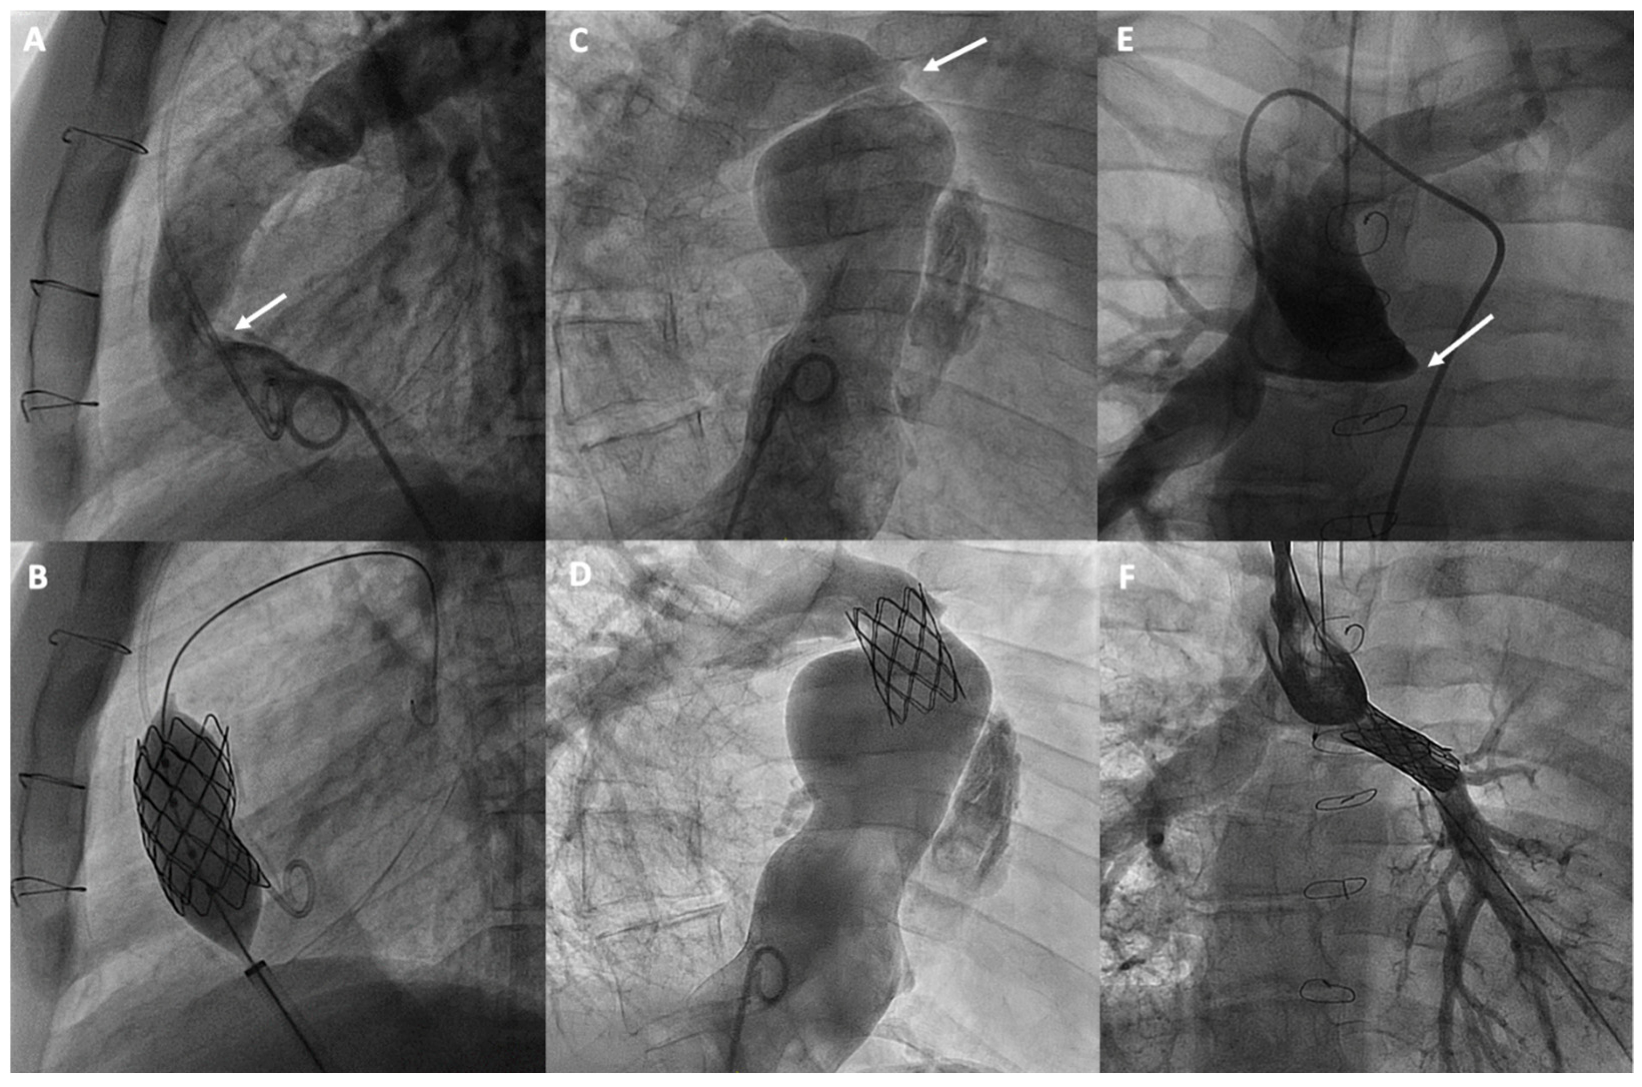

3.1. Management of Fontan Pathway Obstructions

| Fontan Pathway Obstructions | Balloon angioplasty, and especially stenting, are commonly used to treat obstructions in the Fontan pathway and pulmonary branch stenosis. |